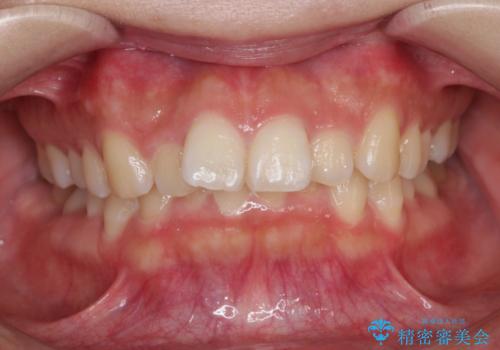

八重歯をインビザラインで非抜歯矯正

- 八重歯を主訴に来院されました。

インビザラインにて奥歯を後方に移動して八重歯が入るスペースを確保してく矯正する計画としました。

八重歯と前歯のガタガタがなくなり、歯並びがきれいになったのと、かみ合わせも改善することができました。